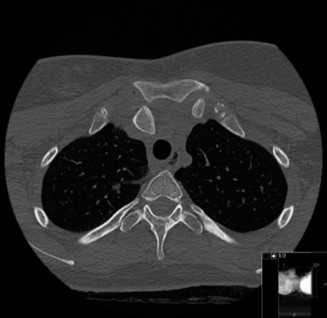

Thorough pre-operative planning begins with advanced imaging. While the initial ED evaluation mandates true orthogonal radiographs (AP and Axillary views) to confirm joint concentricity and rule out fractures, definitive surgical planning requires cross-sectional imaging. Magnetic Resonance Imaging (MRI), preferably an MR Arthrogram with intra-articular gadolinium, is the gold standard for evaluating the soft tissues. It allows for the precise identification of Bankart, ALPSA, and SLAP lesions, assesses the volume and integrity of the capsular tissue, and evaluates the rotator cuff.

To accurately quantify bipolar bone loss, a non-contrast 3D Computed Tomography (CT) scan with digital subtraction of the humeral head is mandatory. Glenoid bone loss is calculated using the "best-fit circle" method on the en face sagittal view of the glenoid. The width of the inferior glenoid is compared to the expected diameter of the intact posterior rim. Simultaneously, the Hill-Sachs lesion is evaluated to determine if it is "on-track" or "off-track." The glenoid track is calculated as 83% of the intact glenoid width, minus the measured anterior glenoid bone loss. If the medial margin of the Hill-Sachs lesion extends medial to this track, it is deemed "off-track" and will engage the anterior glenoid rim during abduction and external rotation, necessitating either a Remplissage or a Latarjet.

Clinical & Radiographic Imaging Archive